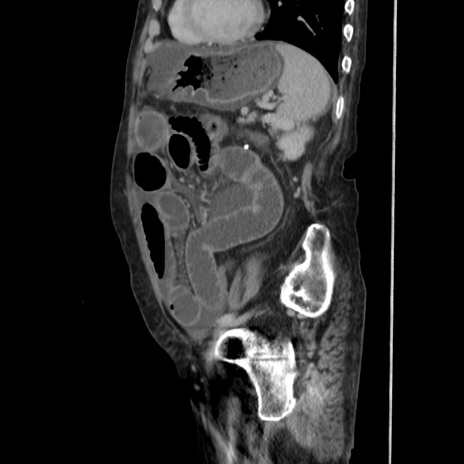

症例31(矢状断像)

【症例】80歳代 女性

【主訴】腹部膨満感

【現病歴】他院にて肝硬変にてフォロー中。1週間前から便秘、腹部膨満感、臍部腫瘤あり受診となる。

【既往歴】肝硬変

【身体所見】腹部膨隆あり、皮膚変化なし、疼痛なし。

【データ】WBC 4600、CRP 0.25